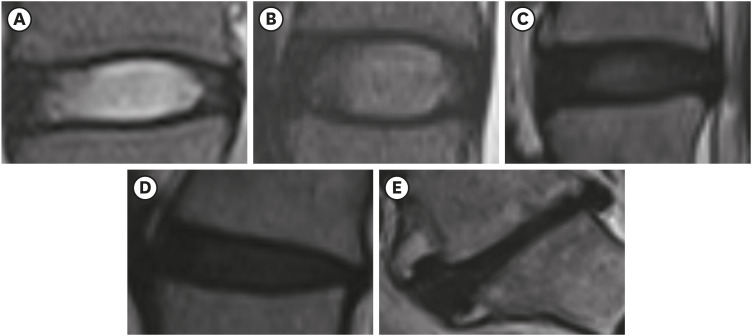

We obtained the participants' lumbar spine images; imaging was conducted using 1.5 Tesla MRI (Avanto; Siemens, Washington, D.C., USA). Sagittal T2-weighted images were assessed to identify disc degeneration at all disc levels from the intervertebral disc between the 1st and 2nd lumbar vertebrae (L1/2) to that between the 5th lumbar and 1st sacral vertebrae (L5/S1). Two researchers (blinded to all demographic and clinical information) evaluated the degree of lumbar disc degeneration based on the Pfirrmann classification system [24]. We defined “collapsed” as a ≥ 50% reduction from the expected value (Fig. 1). In this study, we classified cLD as a case with ≥ 1 grade 5 at any disc level. We calculated the mean Pfirrmann grade from 5 lumbar intervertebral discs. The interobserver reliability of Pfirrmann grade 5, based on quadratic weighted kappa, was 0.763, 0.804, 0.747, 0.732, and 0.804 for L1/2, L2/3, L3/4, L4/5, and L5/S1, respectively. Kappa of cLD was 0.703. Any discrepancy was resolved through discussion between the researchers.

Fig. 1

MRI examples of Pfirrmann grades. (A) Grade 1 defines a homogeneous bright white disc with normal disc height. (B) Grade 2 defines an inhomogeneous white disc with a clear distinction from the annulus fibrosus and normal disc height. (C) Grade 3 defines an inhomogeneous gray disc with an unclear distinction from the annulus fibrosus and normal disc height. (D) Grade 4 defines an inhomogeneous gray-to-black disc without distinction from the annulus fibrosus. (E) Grade 5 defines an inhomogeneous black disc with collapsed intervertebral space.